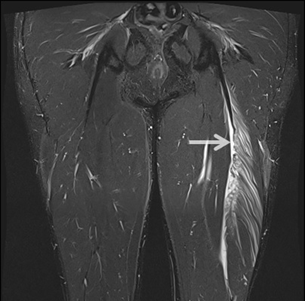

Липосаркома На Бедре Фото 117 фотографий